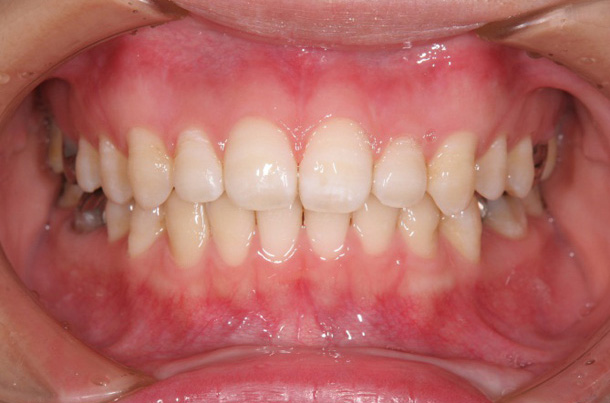

症例3

主訴:下の前歯がガタガタしている

年齢:11歳

診断:下顎前歯の叢生

装置:下顎リンガルアーチ

(リンガルアーチにて永久歯第一大臼歯を固定し、自然萌出交換により叢生の改善)

治療期間:10ヶ月

抜歯:なし

費用:50,000円+税

リンガルアーチセット時

第二小臼歯萌出後